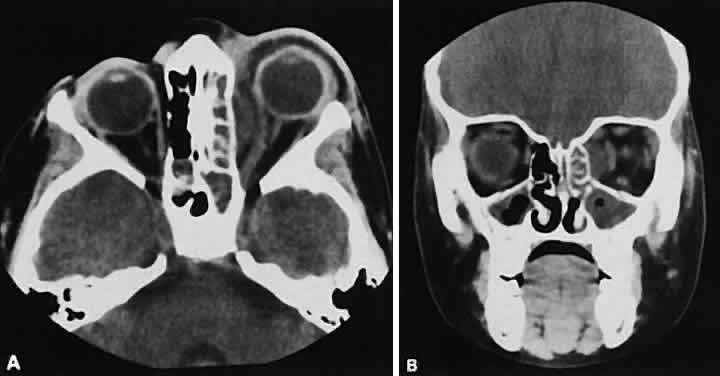

Lymphomatous involvement of the lacrimal gland resembles inflammatory dacryoadenitis radiographically. The enlarged lacrimal gland conforms to the shape of the globe, and the adjacent bone is normal (Fig. 18). We are aware of three high-grade lymphomas that affected the orbit and lacrimal gland and indented the globe, but this is distinctly unusual. Non-Hodgkin's B-cell lymphomas represent the most common type of lymphoma to affect the orbit. Literally any structure in the orbit can be subject to lymphomatous involvement; therefore, a lymphoma should be suspected in the presence of any amorphous isointense infiltrative process.

Fig. 18. Axial (A) and coronal (B) views of lacrimal gland lymphoma. There is homogenous enhancement of the enlarged lacrimal gland. Compared with Fig. 6, there is no difference.